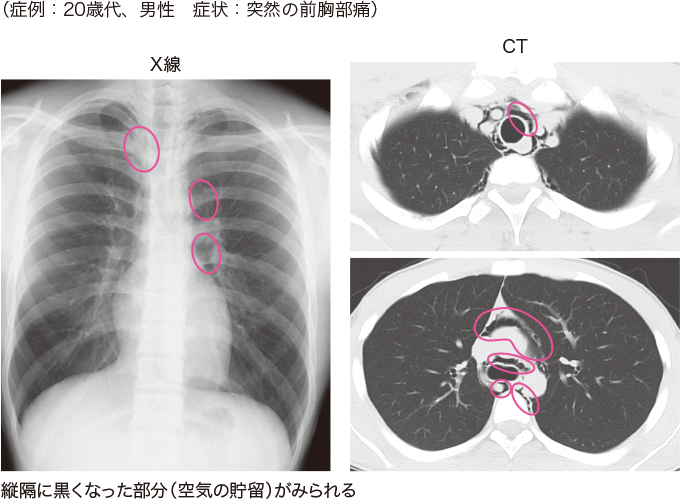

水疱性肺気腫は消失肺症候群と呼ばれることもあります。その理由は、X 線画像では大きなエアポケットにより肺が消滅しているように見えるためです。